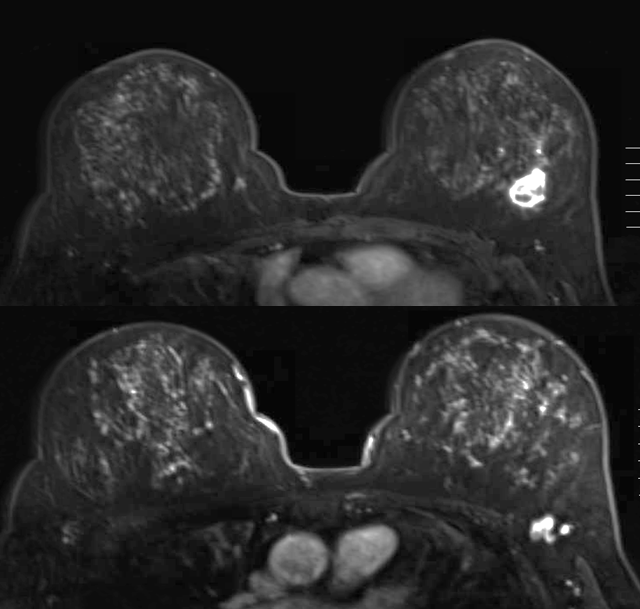

الحالة الأولى: تم اكتشاف كتلة في الثدي الأيسر. ثم تشخيصها بعد عمل خزعة بالأشعة التلفزيونية. تم عمل PET CT بعد ذلك واتضح وجود الكتلة وانتشار لأحد فقرات الظهر. ثم عمل ال MRI ويتضح وجود الكتلة في الجزء الخلفي الخارجي للثدي الأيسر.

تم علاج المريضة بعلاج اشعاعي لمنطقة الفقرة المصابة وعلاج السرطان بالعلاج الكيماوي واختفى بعد ذلك في الرنين المغناطيسي ثم تم استئصاله كاملا والحمدلله.